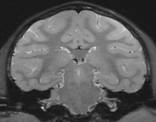

High resolution image of a

monkey brain produced using

a dedicated receiver coil.

Our research deals with magnetic resonance imaging with several focuses. One focus is on high resolution imaging to improve the diagnosis of arthritic diseases as well as to evaluate drug treatment for those diseases. A second focus is on RF coil development to improve image resolution and scan time. Other focuses include: water/fat imaging, brain functional MRI, diffusion-weighted imaging and MR spectroscopy.